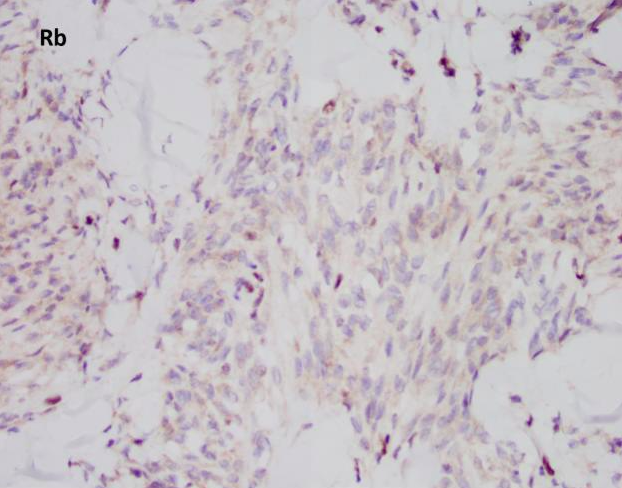

Myofibroblastoma (MFB) is an uncommon myofibroblastic lesion, typically seen in older patients. It occurs in both males and females and usually presents as a slow growing, palpable, painless breast mass. Most lesions are small, 1-4 cm; however, cases of giant myofibroblastomas have been reported. Histologically, the lesion is characterized by a well-circumscribed mass composed of spindle cells intermixed between bundles of hyalanized collagen. Because the neoplasm is myofibroblastic in origin, immunohistochemical markers such as Smooth Muscle Actin (SMA), Muscle Specific Actin (MSA), and Desmin are characteristically positive. Myofibroblastomas are also typically positive for CD34, estrogen receptor (ER), progesterone receptor (PR), and androgen receptor (AR). The cells of interest are negative for cytokeratins. Genetically, the entity is characterized by loss of 13q14 and 16q. As a result, there is inactivation of genes RB1 and FOXO1, and as such, loss of Rb expression via immunohistochemistry. Treatment typically consists of surgical excision with no additional therapy required.

All of the other answer choices may be considered in the differential diagnosis, especially on biopsy. Metaplastic carcinomas can be comprised of spindle cells with or without an epithelioid component. However, the stromal collagen is typically not present and the cytology is much more pleomorphic with frequent mitosis and an infiltrative growth pattern. Additionally, metaplastic carcinomas will be positive for cytokeratin immunohistochemistry and negative for hormone receptors ER/PR/AR, CD34, and desmin/myofibroblastic markers. Phyllodes tumors are also neoplasms of stromal differentiation. Phyllodes tumors, however, show both the presence of spindle cells and benign epithelium, typically creating a “leaf-like” architecture. IHC is positive for CD34 but Rb staining is retained. Pseudoangiomatous stromal hyperplasia (PASH) usually doesn’t form a mass; however, it is a myofibroblastic lesion with a similar staining pattern, SMA, desmin, ER, and PR positive. Histologically PASH has a dense collagenous stroma with prominent slit-like spaces. Additionally, the characteristic genetic alterations found in MFB are not present.